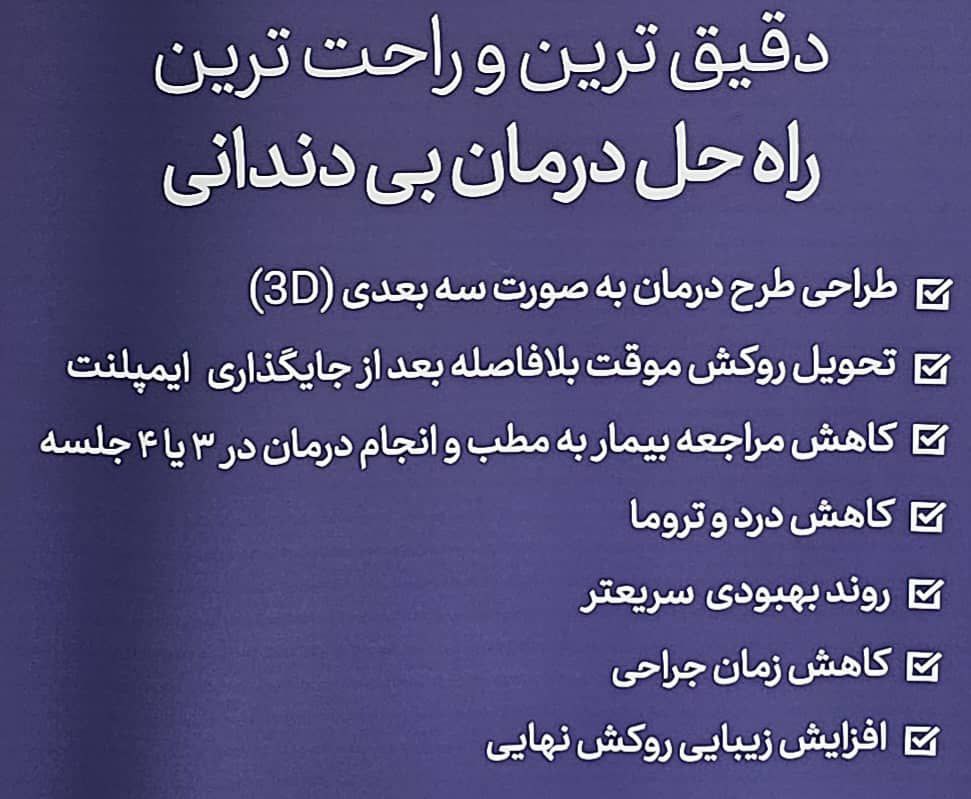

مزایای ایمپلنت دیجیتال:

دقت بالا: موقعیت دقیق ایمپلنت از پیش تعیین میشود و خطر آسیب به بافتها عصبها کاهش مییابد

سرعت بیشتر: مراحل برنامه ریزی و ساخت پروتز سریع تر انجام میشود

نتایج پیشبینی پذیر: طراحی و شبیه سازی قبل از عمل ،به ارائه نتایج قابل اعتماد کمک میکند

کمترین تهاجم: نیاز به برشهای بزرگ کمتر بوده و ترمیم زخم سریعتر است